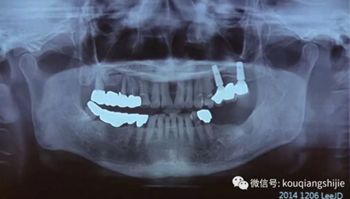

這位患者是2014年來到我們醫(yī)院

從CT上我們可以看到#14,15,17的牙槽骨被牙齒長期的牙周炎破壞的非常嚴重,但是因為當時患者不想拔牙,所以暫時保留下來。

但是1年之后,因為患者實在無法繼續(xù)使用這些牙齒

所以到我們醫(yī)院進行了拔牙

9周后,我們發(fā)現(xiàn)黏膜組織愈合的非常好

11周翻開黏膜,我們發(fā)現(xiàn)形成的骨已經(jīng)完全滿足我們種植的需要

我們正常進行種植,并在縫隙處放置骨粉。